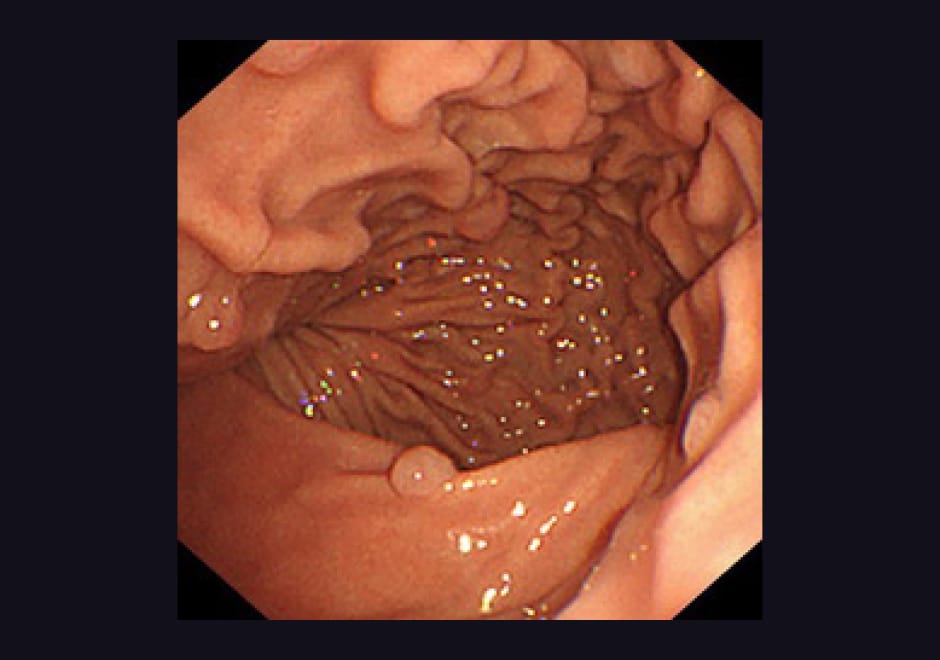

胃内視鏡検査(胃カメラ)

胃がん・胃潰瘍・急性胃炎・ポリープ・食道癌・逆流性食道炎などを調べる検査です。当院では次の3通りの方法の中から患者様に選んでいただくことができます。

| 胃潰瘍・十二指腸潰瘍 急性胃腸炎・胃がん | 当院で胃内視鏡をして診断をつけます。胃炎や胃潰瘍はピロリ菌が原因となる事が多く、検査で陽性の診断が出れば、内服薬で除菌を行います。早期胃癌だけでなく進行胃癌でも症状がないことがあります。内視鏡による胃癌検診も当院で行なっています。 |

| 逆流性食道炎・胸やけ 喉の違和感・食道がん | 逆流性食道炎は胃液が食道に逆流して症状が起こります。症状が多彩な疾患で喉の違和感・胸焼け・胸痛・腹痛・嘔気などの症状が出ます。食道癌や胃癌でも同じ症状が出ることがあり注意が必要です。胃内視鏡で正確な診断をつける事が出来ます。逆流性食道炎は内服薬と食事療法でほとんどの方が治ります。食道がんは初期では症状がなく、進行すると食事が喉に引っかかるようになります。胃内視鏡で胃と同時に検査出来ます。 |